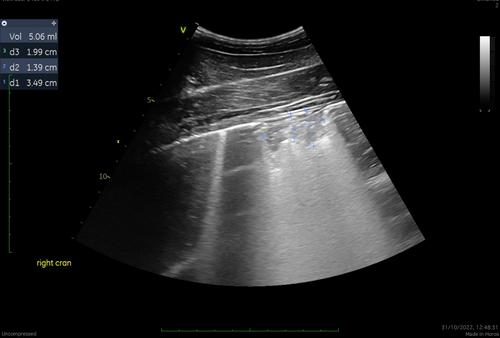

Abstract Image